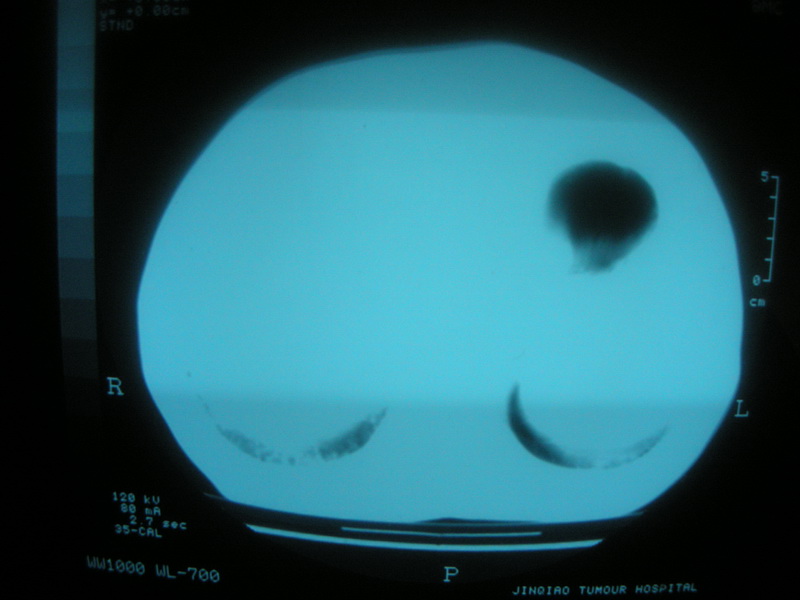

标题: CT11692:男,63岁,糖尿病史15年.抗炎治疗7天,病情 [打印本页]

标题: CT11692:男,63岁,糖尿病史15年.抗炎治疗7天,病情

请老师看看是结核还是炎症?

根据影像表现及临床符合结核感染。

双肺继发性肺结核伴感染!